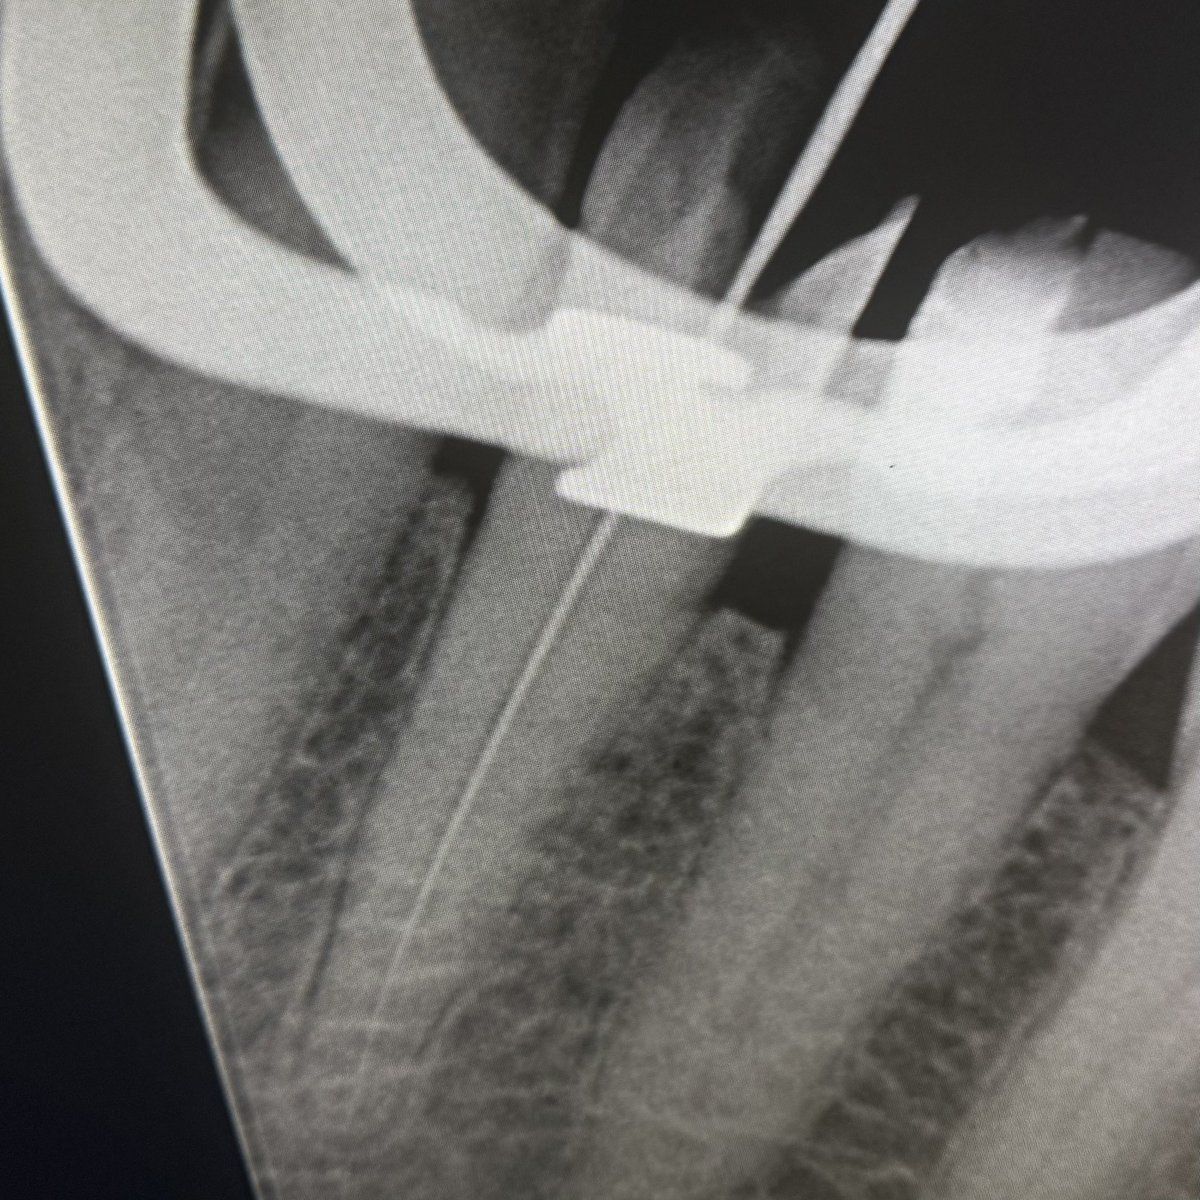

حالة جديدة اليوم ❤️

Root Canal Treatment for #36

The patient complained of severe pain,after examination we decided to do RCT.

Dx: SIP,NAP

ML wall is replaced then started RCT.

Single Cone and BC Sealer are used